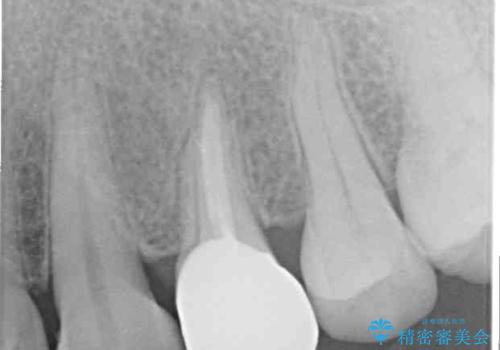

診査の結果、既に歯の神経は失活しており、レントゲンより根尖部に病変を認めました。

補綴後6ヶ月経過しレントゲンを撮影したところ、根尖周辺の病変が消失していることが確認できました。